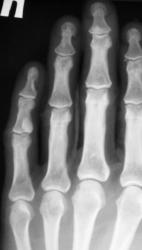

Катенёв Валенти... Дата публикации 19.06.2009, 20:43 Ваше мнение коллеги по поводу локального "уплотнения костной ткани" в средней фаланге 5 пальца левой кисти. Эностоз? Ваше мнение коллеги? Пт, 19/06/2009 - 20:46 #1 Глазков Игорь А... Не на сайте Был на сайте: 11 месяцев 3 недели назад Зарегистрирован: 19.12.2008 - 20:41 Публикации: 1597 что эностоз, но неплохо бы узнать возраст пациента. Прийди к Себе Пт, 19/06/2009 - 20:52 #2 Катенёв Валенти... Не на сайте Был на сайте: 7 лет 3 месяцев назад Зарегистрирован: 22.03.2008 - 22:15 Публикации: 54876 Пациент возраста около 30-ти лет.